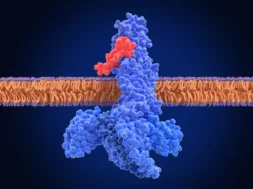

Επί του παρόντος, δεν μπορείτε να πάτε στο γιατρό και να ζητήσετε να πάρετε το εμβόλιο. Ωστόσο, δεν πρέπει να εκπλαγείτε αν συμβεί νωρίτερα από ό, τι ελπίζατε ποτέ. Οι ερευνητές πιστεύουν ότι οι ασθενείς με Alzheimer έχουν πλάκες που περιέχουν β-αμυλοειδές, μια κολλώδη εγκεφαλική πρωτεΐνη που σχηματίζεται στον εγκέφαλο.

Η United Neuroscience, οι ερευνητές της, πιστεύουν ότι έχουν βρει ένα εμβόλιο που φαίνεται να βελτιώνει τη λειτουργία του εγκεφάλου και να μειώνει την πλάκα πρωτεΐνης που κολλάει τους νευρώνες τους. «Επιτυγχάνουμε πολύ περισσότερα από ένα εικονικό φάρμακο» δήλωσε ο διευθύνων σύμβουλος της Neuroscience Mei Mei Hu στο News Bloomberg. “Δεν μπορούμε να έχουμε ακόμα αξιώσεις, αλλά είμαστε προς τη σωστή κατεύθυνση.”